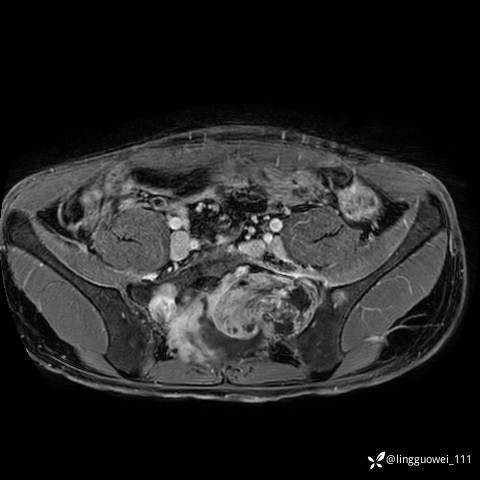

男,25岁,腰痛4年,加重左下肢痛5天,先上传X光片,第2天再上传CT。MR

MR:(忘记截图常规序列,不过应该不影响诊断)